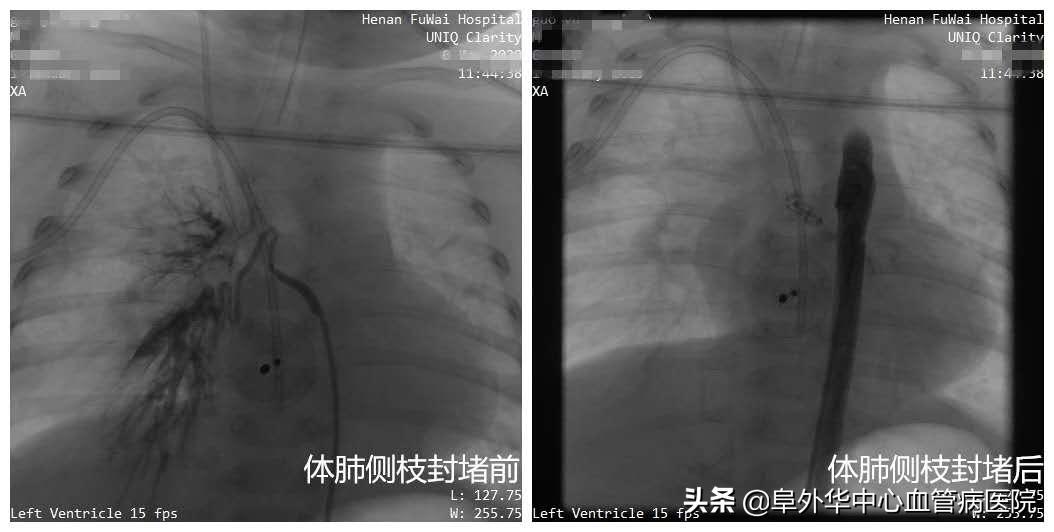

范太兵教授像福尔摩斯一样,大胆推测、抽丝剥茧,逐步逼近事情的真相。进一步掌握证据后,专家们心里有了底。无影灯下,范太兵教授、宋书波博士等专家开始实施手术。在先进的杂交手术室,进行术中动脉造影,打入造影剂后果然发现,小患者有粗大体肺侧枝形成,直径足有4毫米以上!正是这根本来不该存在的血管,导致血液灌注肺部,它才是引起肺炎和气喘的真正元凶,而室间隔缺损(中轻度)和动脉导管未闭不会造成这样的结果。

紧接着,专家们一鼓作气,为孩子实施了“房间隔缺损微创封堵+体肺侧枝封堵术”。整个手术过程,仅有1.5个小时。范太兵教授等专家不但抽丝剥茧找到“真凶”,并且用微创手术代替开胸手术,不但大大降低创伤,并且为患者节省了大量费用。